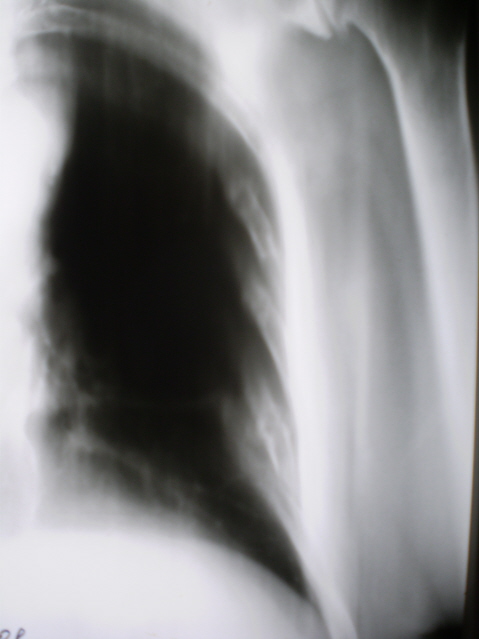

"Избыточная импергнация" солями извести хрящевой части 1 ребра справа, которая обусловила наличие синдрома "Круглая тень", как следствие  разрыва реберно-грудинного сочленения. Правосторонний экссудативный плеврит.